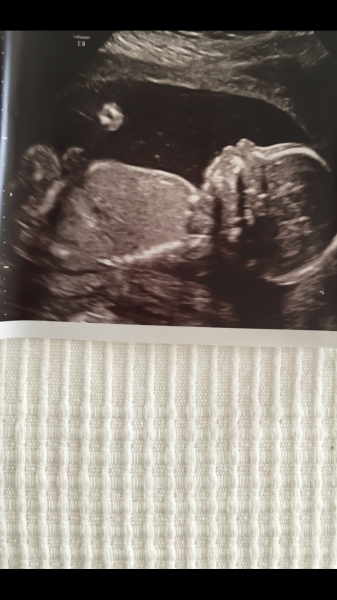

Hej! Är de någon som vågar sig på en gissning när det kommer till kön, är i v13

Vill ngn gissa den är i vecka 19(18+6 ) beräkna 18/2-18

Skulle vara jättekul om någon ville gissa! Vecka 12+5 på dessa bilder! är i vecka 20 nu och får förhoppningsvis reda på svaret nästa vecka!